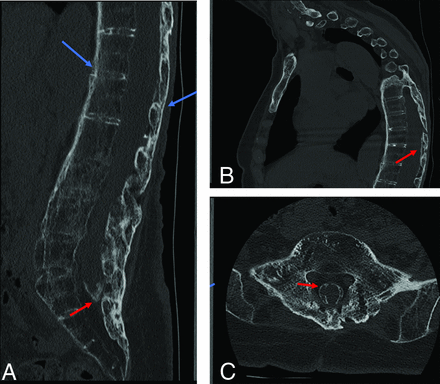

CT images from a 66-year-old female patient with back pain and stiffness. Sagittal (A and B) and axial (C) CT demonstrate features of spinal ankylosis relating to inflammatory spondyloathropathy (blue arrows). AO is evident by thick peripheral ossification of the meninges most prominent at the tip of the thecal sac; however, it can also be seen in the thoracic spine (red arrows).